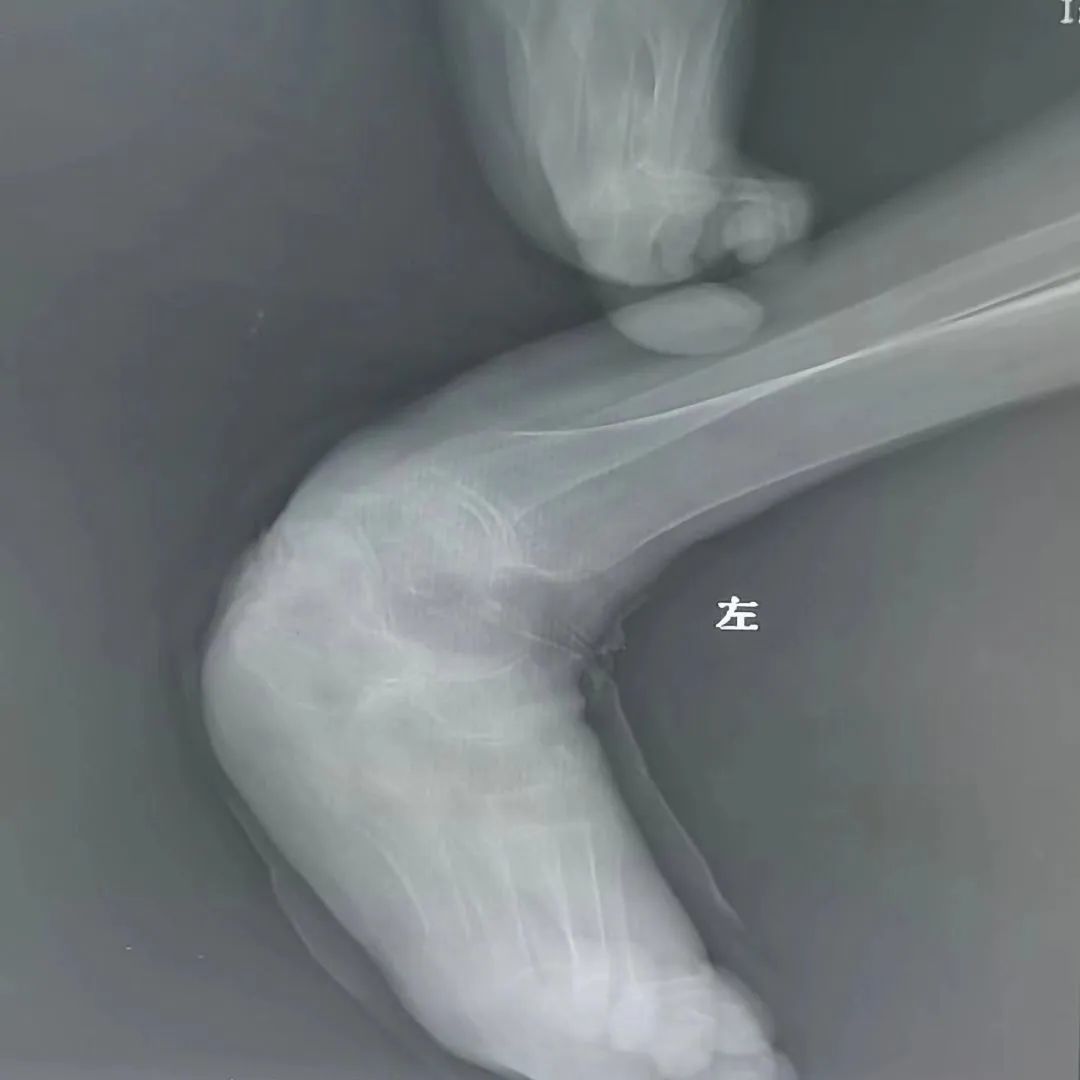

该患者伴有严重的类风湿性关节炎并肢体畸形